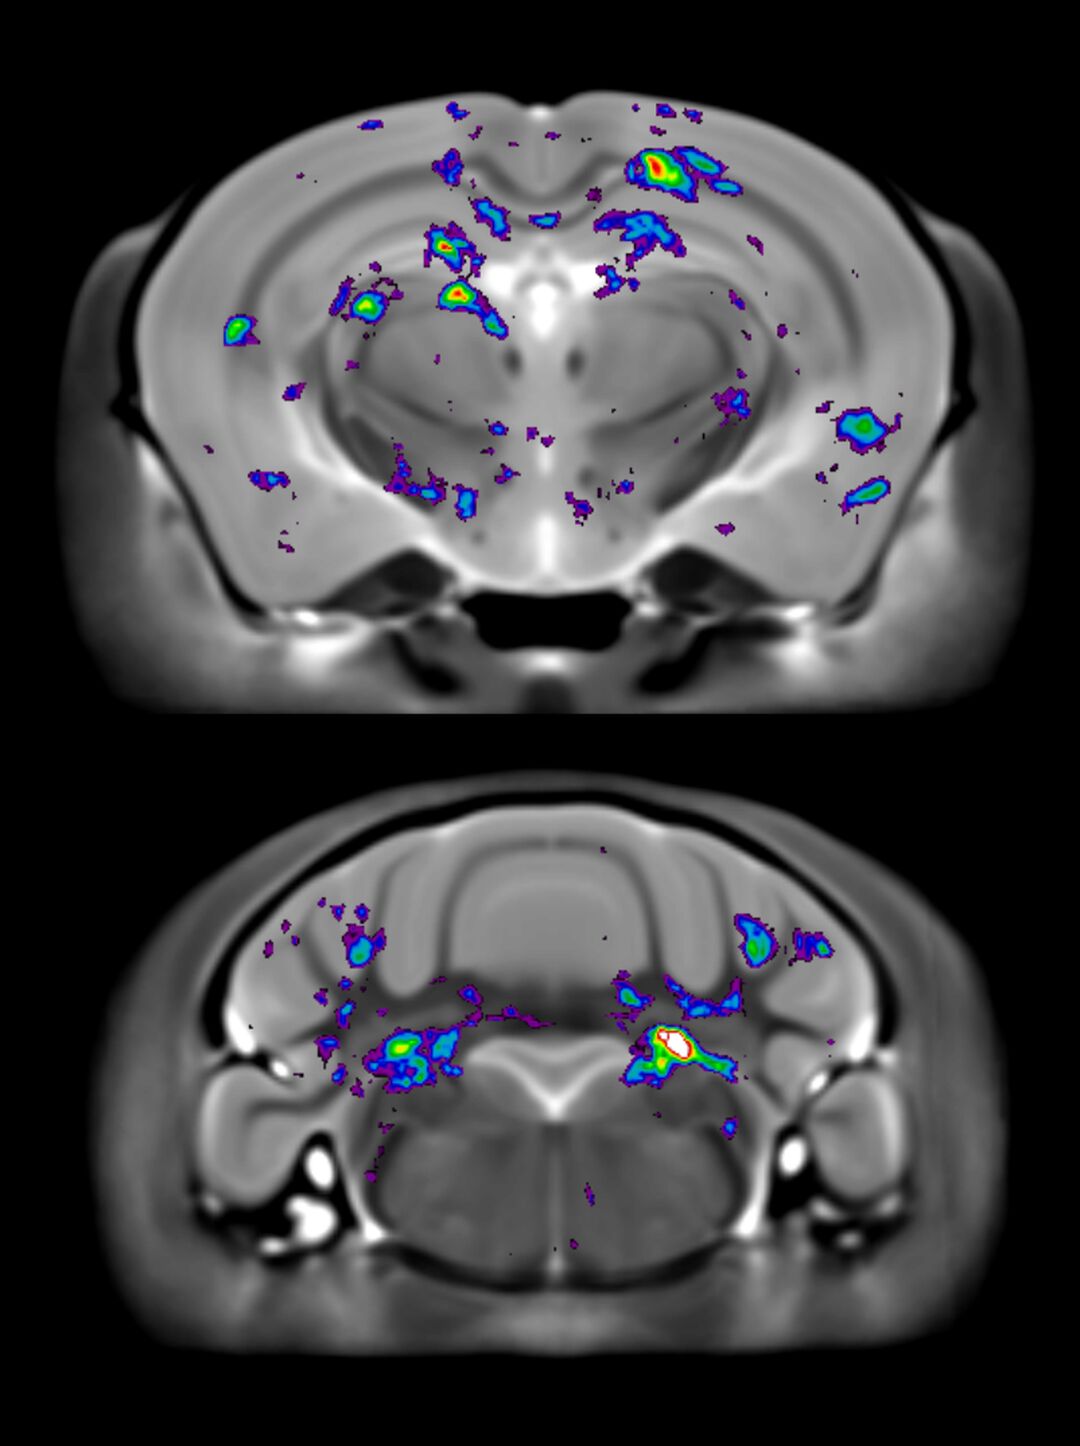

The open data release includes 31 mouse models, representing 23 genotypes from an ongoing study with currently more than 90 mouse models by POND, OBI’s research program on neurodevelopmental disorders. Drs. Jason Lerch, Jacob Ellegood, Mark Henkelman and their team at SickKids collaborated with multiple national and international research groups to collect MR images with genetic mutations that are known to be associated with autism. The images identify key brain areas affected by autism and capture the complex changes in the brain structure across the mouse model, providing key insights when comparing differences found in people with autism.